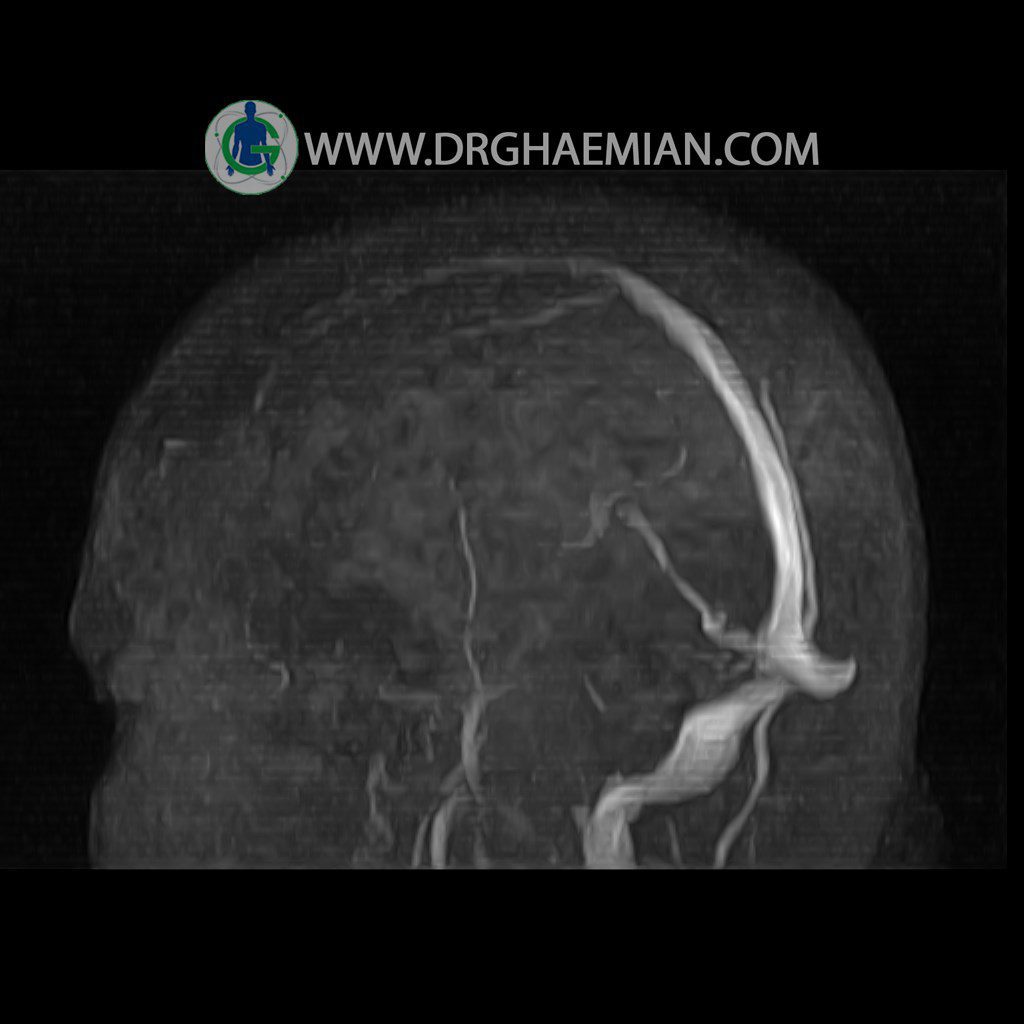

ام آر وی یک روش تصویربرداری دقیق و غیر تهاجمی است که برای معاینه ورید های بدن و ارزیابی سلامت رگ ها استفاده می شود. ورید ها خون را از اعضای بدن به قلب باز می گرداند تا دوباره اکسیژن و مواد مغذی به خون داده شود. ام آر وی جریان خون را ارزیابی و موارد غیرعادی مضر مانند لخته های خونی را شناسایی می کند. در این کیس ترومبوز انسدادی مغز بیمار مشاهده می شود.

CRANIAL MRV

(with & without contrast )

Technique: TOF ( time of flight ).

Images of the venous cranial vessels demonstrates a superior sagittal sinus of normal caliber with normal arrangement of draining superficial cerebral veins.

The great cerebral vein Galen inferior sagittal , straight sinuses appear normal.

The right transverse and sigmoid sinuses present a normal caliber.

The other evaluable deep cerebral veins , basal and labbe are normally developed and patent.

No venous segments contain flow voids or filling defects.

The other evaluable portions of the neurocranium show no abnormalities.

– Nonvisualized left transverese sinus with narrowing of left sigmoid sinus suggestive for obstructive thrombosis

is seen